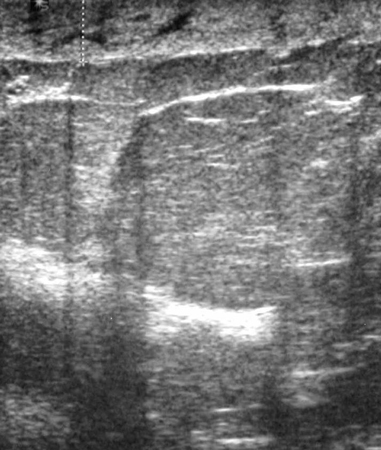

Ultrasonographic image of skin thickening in patient with inflammatory breast cancer

Courtesy of Dr Nancy Pile, University of Louisville; used with permission